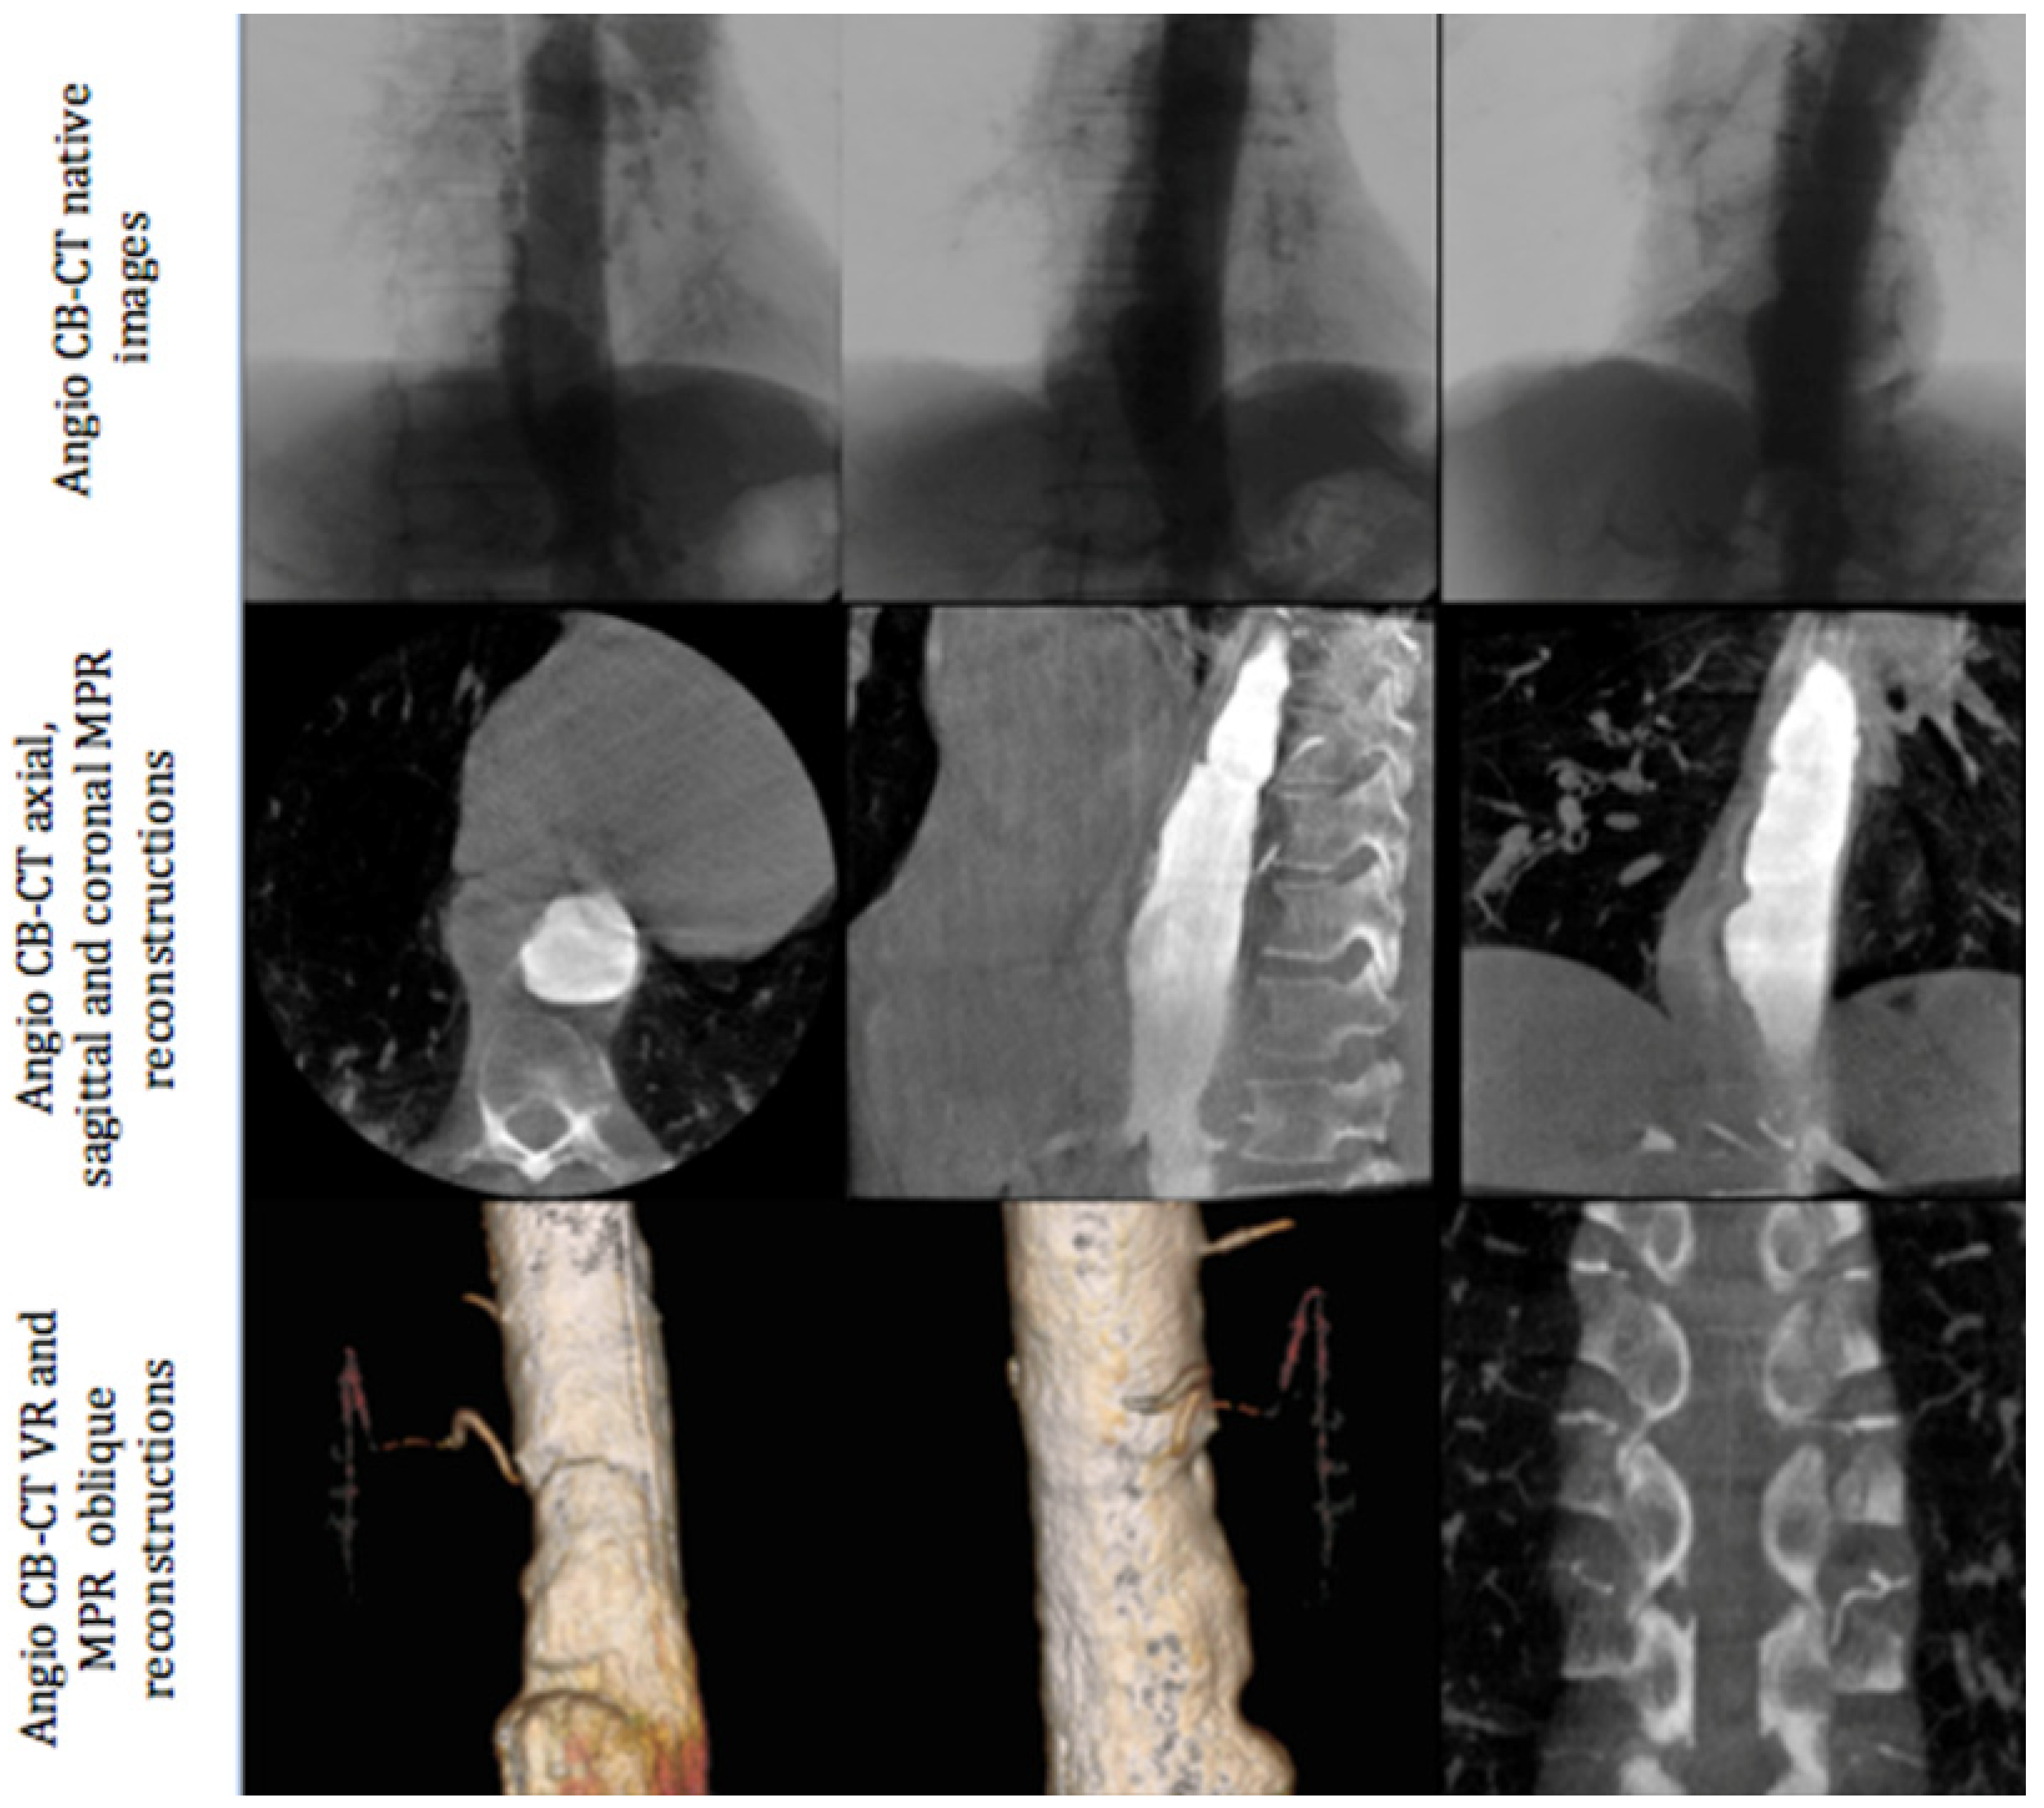

2.2. Diagnostic Angiography Procedure